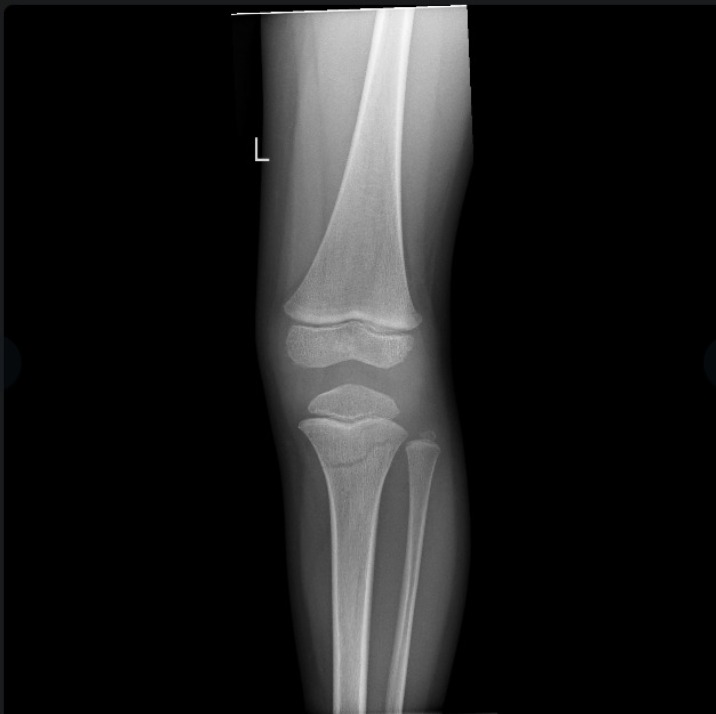

את קריאתו מגבה היועץ הרפואי בתמונות של שברים אמיתיות מהיממה האחרונה. "לא כדי להפחיד, אלא כדי להזכיר: החיים שווים הרבה יותר מהרגע המסוכן הזה".

בהתייחסו לתמונות השברים אותן הציג הוא אומר "כל תמונה של שבר היא סיפור של חיים שנעצרו בבת אחת – ניתוחים, גבס, שיקום ממושך, כאבים בלתי פוסקים ואובדן שגרה. תראו לעשות הכל, בעיקר המבוגרים, בכדי שלא להגיע לרגעים הללו חלילה".